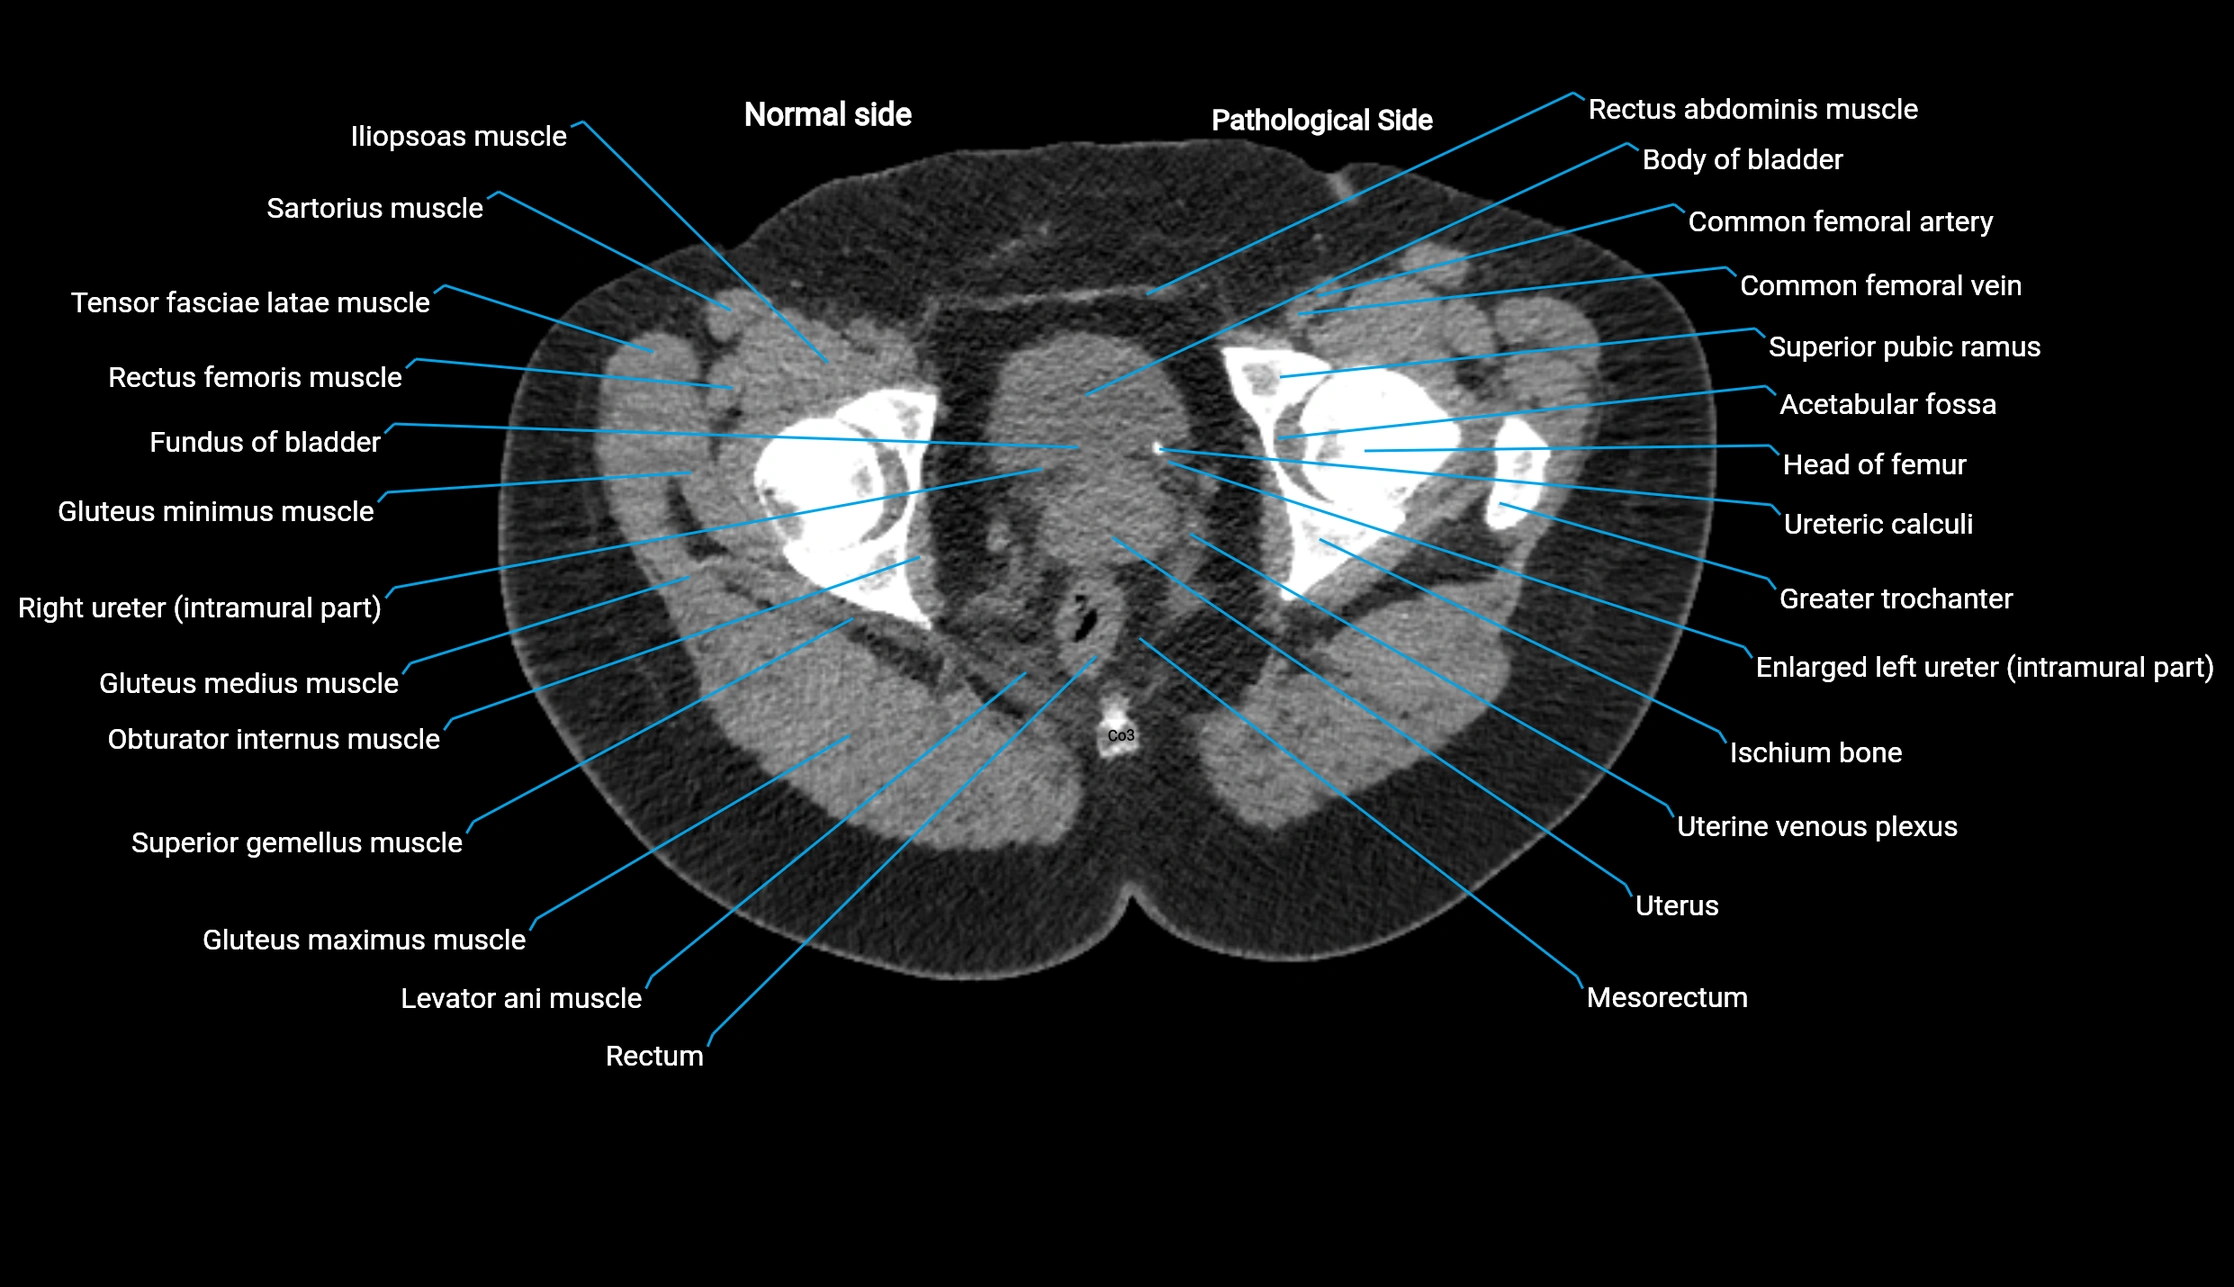

CT image

image